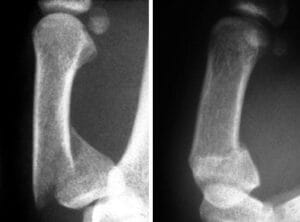

Extra-articular Fracture

- Usually at meta-diaphyseal junction

- Flexor pollicis longus tends to pull the distal fragment into flexion

- Abductor pollicis holds the proximal fragment in abduction

Rolando Fracture

- Fracture line into the joint surface

- Y or T shaped fracture line

- Multiple fragments